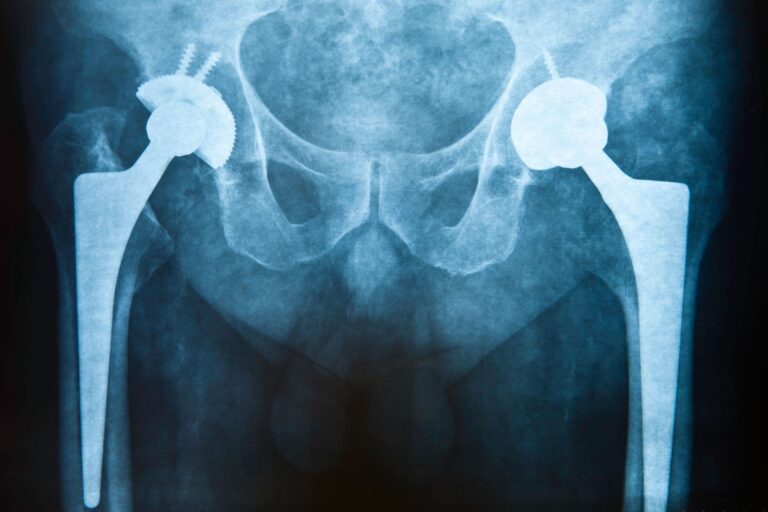

Ezért fontos a csípőprotézis műtét utáni gyógytorna!

A csípőprotézis beültetése mára az egyik leggyakoribb ortopéd beavatkozásnak számít, amelynek segítségével a csípőfájdalom megszüntethető, a mozgásképesség pedig helyreállítható. Ha az operációt követően hamarabb fel szeretnél épülni, akkor a csípőprotézis műtét utáni gyógytorna jelenti a megoldást. Hogyan történik a rehabilitáció,…